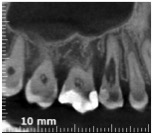

Allora per capirci qualcosa in più ho fatto una cone beam.

A questo punto mi sono chiesto:

“possibile però che un difetto perfettamente identificabile e raggiungibile con microsopio o anche solo con occhialini ingrandenti, sia qualcosa di fronte al quale arrendersi?”

Del resto Heithersay operava negli anni antecedenti al 1999, quando ingrandimenti e microscopio non erano così diffusi e nemmeno l’utilizzo di scansioni tridimensionali dei denti. E se leggi l’articolo in cui descrive la tecnica che utilizzava vedrai che rabbrividirai. Con quella tecnica antidiluviana mi stupisco che abbia avuto un successo così alto!

Come potrai vedere in questo video, il mio pensiero non faceva una piega. Con microsopio e cone beam operare casi del genere è una cosa è perfettamente fattibile e, ti dirò, non è nemmeno difficile.